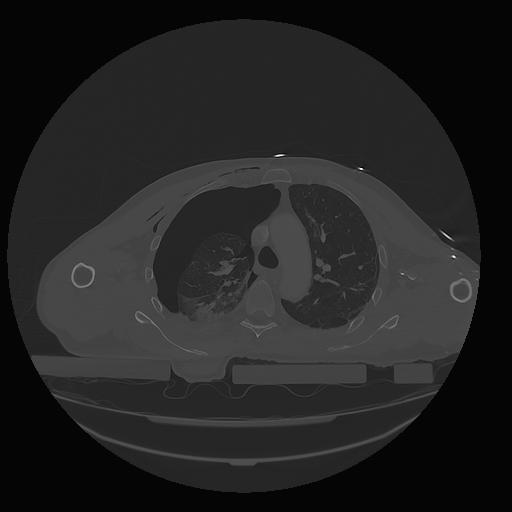

31 PULMON,CE,Vol,1.0,PULMON,,